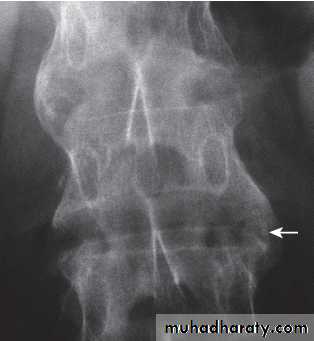

In chronic or recurrent disease, Xrays show periarticular osteoporosis, joint space narrowing and proliferative erosions.

Another characteristic feature is periostitis, especially of metatarsals, phalanges and pelvis, and large, ‘fluffy’ calcaneal spurs.

In contrast to AS, radiographic sacroiliitis is often asymmetrical and sometimes unilateral, and syndesmophytes are predominantly coarse and asymmetrical, often extending beyond the contours of the annulus (‘nonmarginal’)